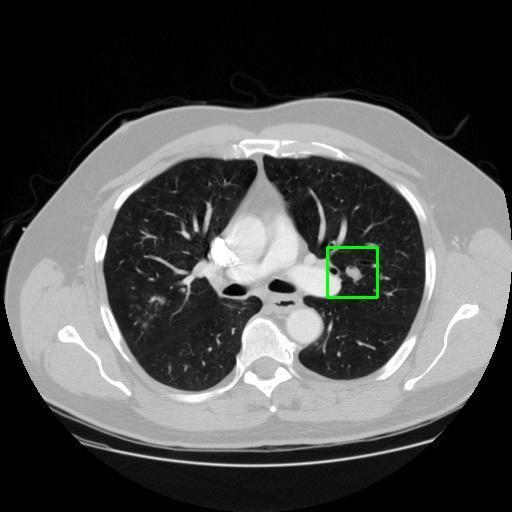

We developed an AI-based system using deep learning models for analyzing lung CT scans to detect and classify pulmonary nodules. We chose the YOLOv11 architecture for its enhanced object detection capability and adapted it specifically for medical imaging, incorporating pixel-level precision and severity classification.

Classification into three severity levels with colored bounding boxes.

Designed a severity classification system that categorizes nodules into null, moderate, and severe using colored bounding boxes, assisting in rapid clinical decision-making.